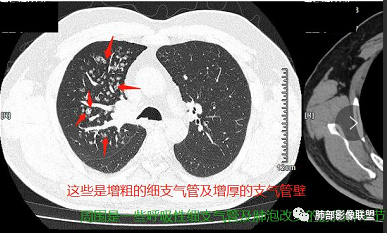

右气管腔内结节,右肺门肿物,有钙化,右侧肺内多发气腔结节,散在,左肺部分支气管壁增厚,首先分析气管内结节,多考虑1鳞癌,形态规则,边缘光滑,宽基底,不太支持,远端阻塞性炎症不典型,2类癌,冰山一角和冰山分离了,不太支持3结核,多为支气管壁广泛增厚钙化,形成结节少,但是肺门肿块有钙化,可作为结核支持点,4黏痰,不像。其他不太懂了,肺内多发磨玻璃结节,并可见支气管手指状扩张,综合分析影像,考虑感染性病变,结核?有没有这样子的气管曲霉呢?向老师们学习。

男,52。间断咳嗽、咳痰2周,加重3天。胸部CT:右主、右上叶支气管多发软组织影,跳跃不连续,内可见小环状高密度,点状钙化,管壁破坏,上叶支气管堵塞,远端分支粘液栓,可见小支气管管壁增厚、管腔狭窄,沿支气管分布多发结节,无大片炎症不张。考虑:TB?NTM?鉴别Ca并阻塞性炎症。

右肺上叶支气管开口见阻塞物影及强化,息肉样向腔内外浸润性生长,并有颗粒钙化,右肺上叶段支气管主干增粗及密度增高,见指套征,支气管血管旁见多发小斑点,小斑片影阻塞性炎性病灶〈小花小草表现〉,支气管镜示新生物血供丰富(结核完全排除),方向恶性,符合鳞癌特点,与小细胞Ca鉴定,临床专科支气管镜取材活检明确诊断。

腔内肿物,强化不均匀,强化程度为轻中度强化(CT值增加25HU),且强化特点为快进快出,右肺上叶支气管责任区域的阻塞性炎症加痰栓(气管镜也证实右上叶支气管内痰多)。这些均明确指向鳞癌。

一点不异常啊,分布在阻塞责任气管区域的支气管增粗伴腺泡结节(细支气管腔内及肺泡内阻塞性炎症伴痰栓),只不过还没有大片实变而已。@韩平     临沂市人民医院呼吸科